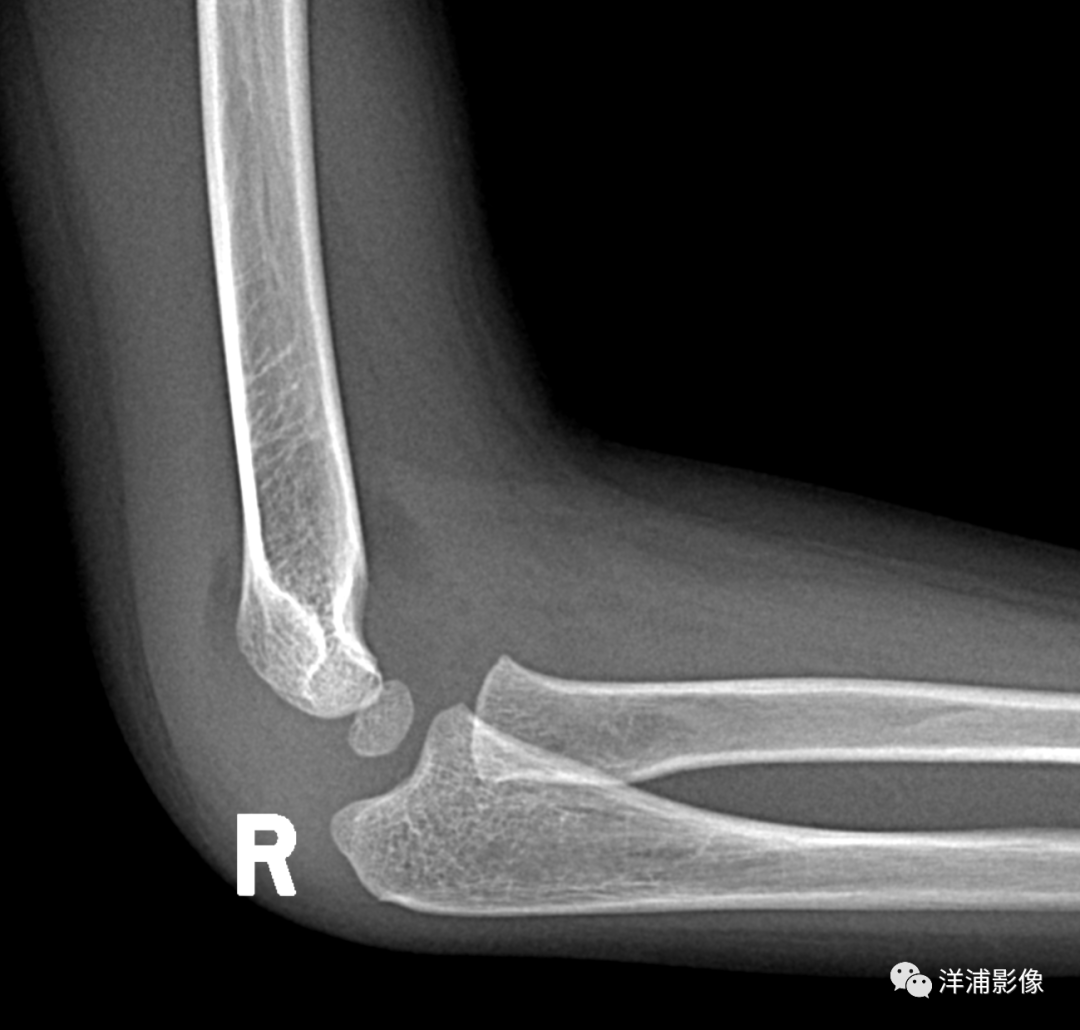

男,4岁,右肘外伤:

脂肪垫通常可在X线平片上显示,但当急性创伤导致软组织肿胀和出血时,脂肪垫可能移位或显示不清。在已知的众多脂肪垫中,目前最有意义的是肘关节囊内脂肪垫和膝关节髌上脂肪垫。当肘后脂肪垫及帆状前脂肪垫显现时,可诊断此为肘关节积液。肘后脂肪垫的显示强烈提示关节囊内隐匿性骨折,但1/4的患者在随访中无阳性发现。

脂肪垫征(fat pad sign):又称帆船征(Sailing sign) 或八字征;细微的软组织表现是骨折的标志,不应漏掉。前后脂肪垫移位提示肘关节内的积血、积液改变,使关节滑膜、脂肪垫被推移,在侧位片上呈“船帆”状;虽然有时肘关节X片中看不到骨折线,但是出现前脂肪垫征时强烈提示有桡骨小头骨折。

脂肪垫征≠骨折,只是说骨折的概率明显增大。

部分研究表明前脂肪垫征(anterior fat pad sign)发生关节内骨折的概率为70-80%。后脂肪垫征(posterior fat pad sign)发生关节内骨折的概率达90%。